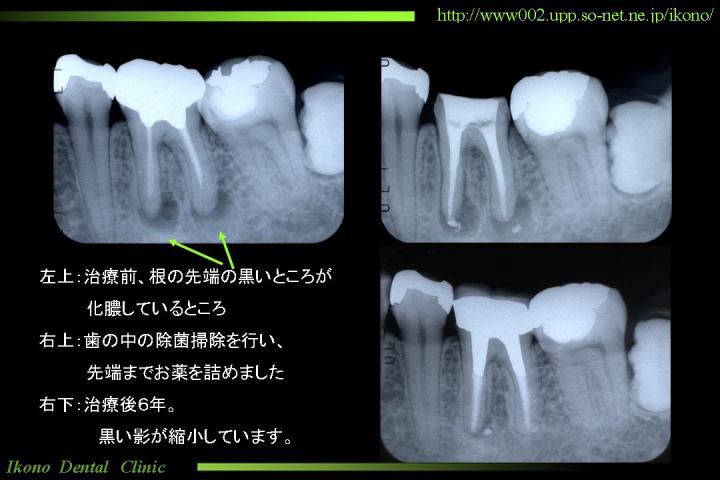

「神経を一度取ればもう痛まない」と誤解なさっているのだと思います。図1

このようなときは「歯が浮いたようになって、痛くて噛めない」状態になります。これは歯の中の神経が痛んでいるわけではなく、歯の周囲の組織が痛んでいるのです。(図1)

目に見えない、地味な治療ですが、きちっと治療すれば神経を取った後のトラブルはずっと少なくなります。(図2)

クリックすると拡大してご覧になれます

歯の根っこが化膿した状態

図1

歯の神経治療のレントゲン写真

図2